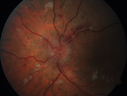

Sickle Retinopathy - Chronic retinal detachment OS - Proliferation OD396 views40 year old with known SC disease. Failed to return 4 years ago for treatment and lost ision in the left eye. Then returned for one visit and refused further treatment.Jan 28, 2019

|